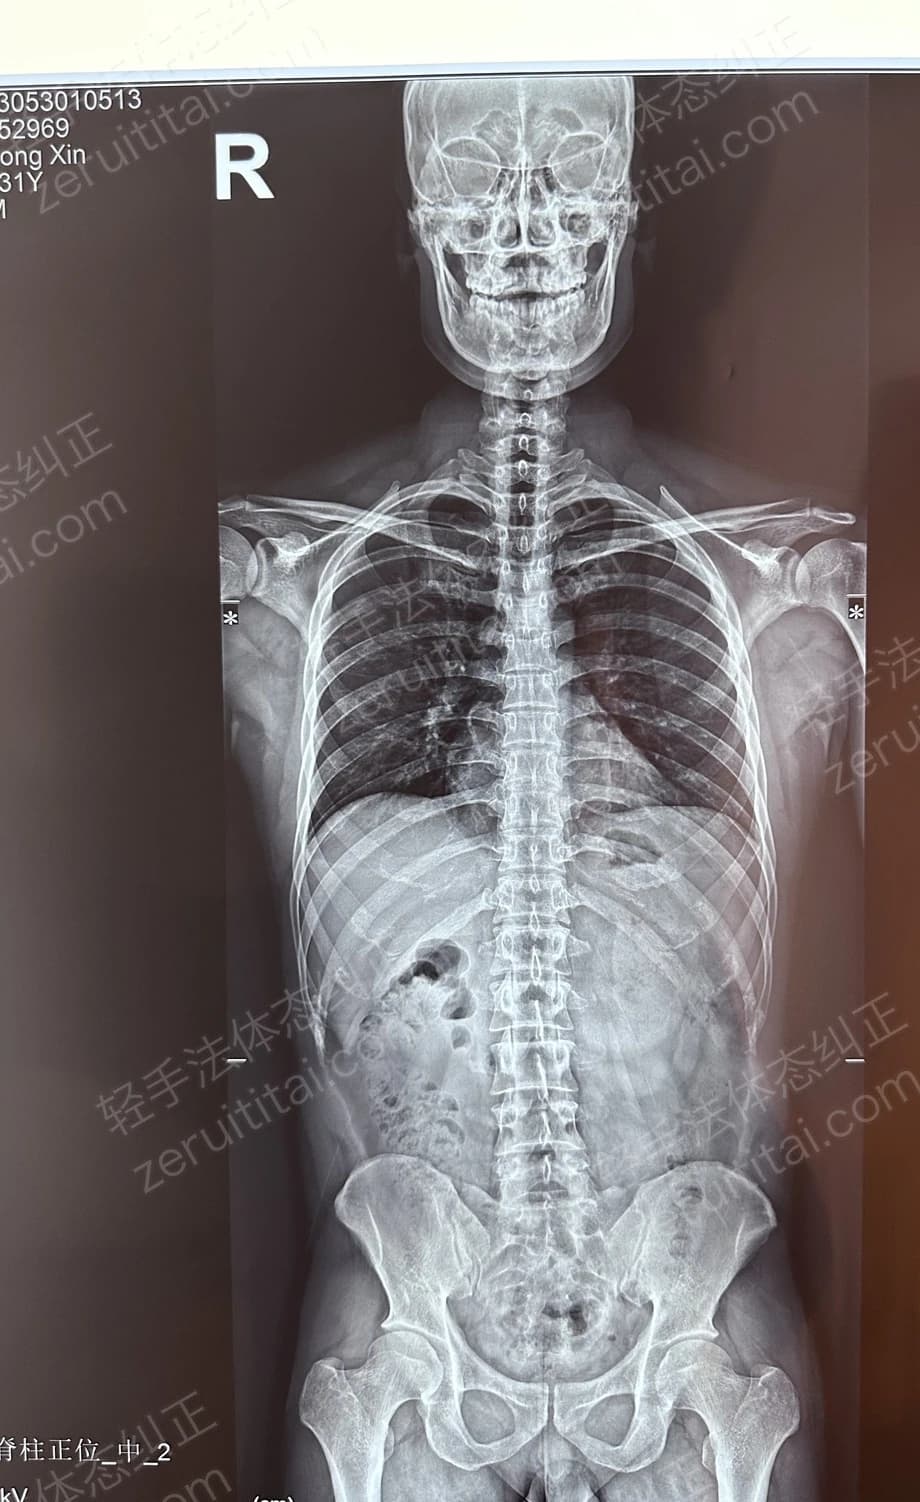

2024.12.18

第 6 次记录

第 6 次记录2024.12.18

正面 X 光